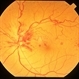

- hemi CRVO, neovascularization elsewhere (NVE)

- A 59-year-old man with DM for 18 years operated for mature cataract. Post op left eye had a visual acuity of 20/80. Wide field swept source OCTA revealed gross vessel wipe out in inferior hemi quadrant with branching out neovascular frond inferior to disc with terminal loops, The patient underwent Anti VEGF injection followed by OCTA guided sectoral retinal photocoagulation.Image J software used here to generate reverse image that sharply delineates the non perfusion area.